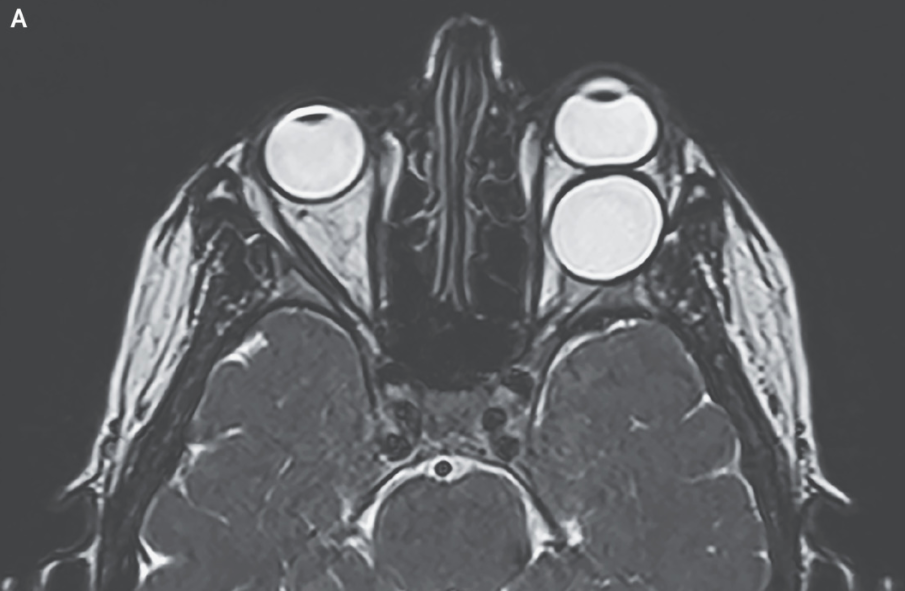

Eye Bulging Out Of Socket Exophthalmos, also known as proptosis or bulging eye, is a condition characterized by the protrusion of one or both eyes from their normal position within the eye sockets. If one of your eyes has been sticking out or bulging lately, this could be a sign of a brain tumor, eye tumor or sinus tumor. Common causes include graves’ disease and orbital cellulitis. Bulging eyes, also called exophthalmos or proptosis, is when one or both of your eyes protrude from their natural position. When an eye protrudes, this is called. If your eyes pop out of their sockets, the first thing to do is dial 911 or your locality’s emergency number to dispatch medics. It's important to note that exophthalmos itself is not a specific condition but rather a sign of an underlying disorder. Proptosis and exophthalmos are the medical terms used to. Exophthalmos, also known as proptosis or bulging eye, is a condition characterized by the protrusion of one or both eyes from their normal position within the eye sockets. Bulging eyes, also called exophthalmos or proptosis, occurs when one or both eyeballs protrude from the eye socket. Eyes that bulge, or protrude out of their normal position, could be a sign of a serious medical condition.

Bulging eyes, also called exophthalmos or proptosis, is when one or both of your eyes protrude from their natural position. If one of your eyes has been sticking out or bulging lately, this could be a sign of a brain tumor, eye tumor or sinus tumor. If your eyes pop out of their sockets, the first thing to do is dial 911 or your locality’s emergency number to dispatch medics. Eyes that bulge, or protrude out of their normal position, could be a sign of a serious medical condition. When an eye protrudes, this is called. Bulging eyes, also called exophthalmos or proptosis, occurs when one or both eyeballs protrude from the eye socket. It's important to note that exophthalmos itself is not a specific condition but rather a sign of an underlying disorder. Common causes include graves’ disease and orbital cellulitis. Exophthalmos, also known as proptosis or bulging eye, is a condition characterized by the protrusion of one or both eyes from their normal position within the eye sockets. Proptosis and exophthalmos are the medical terms used to.